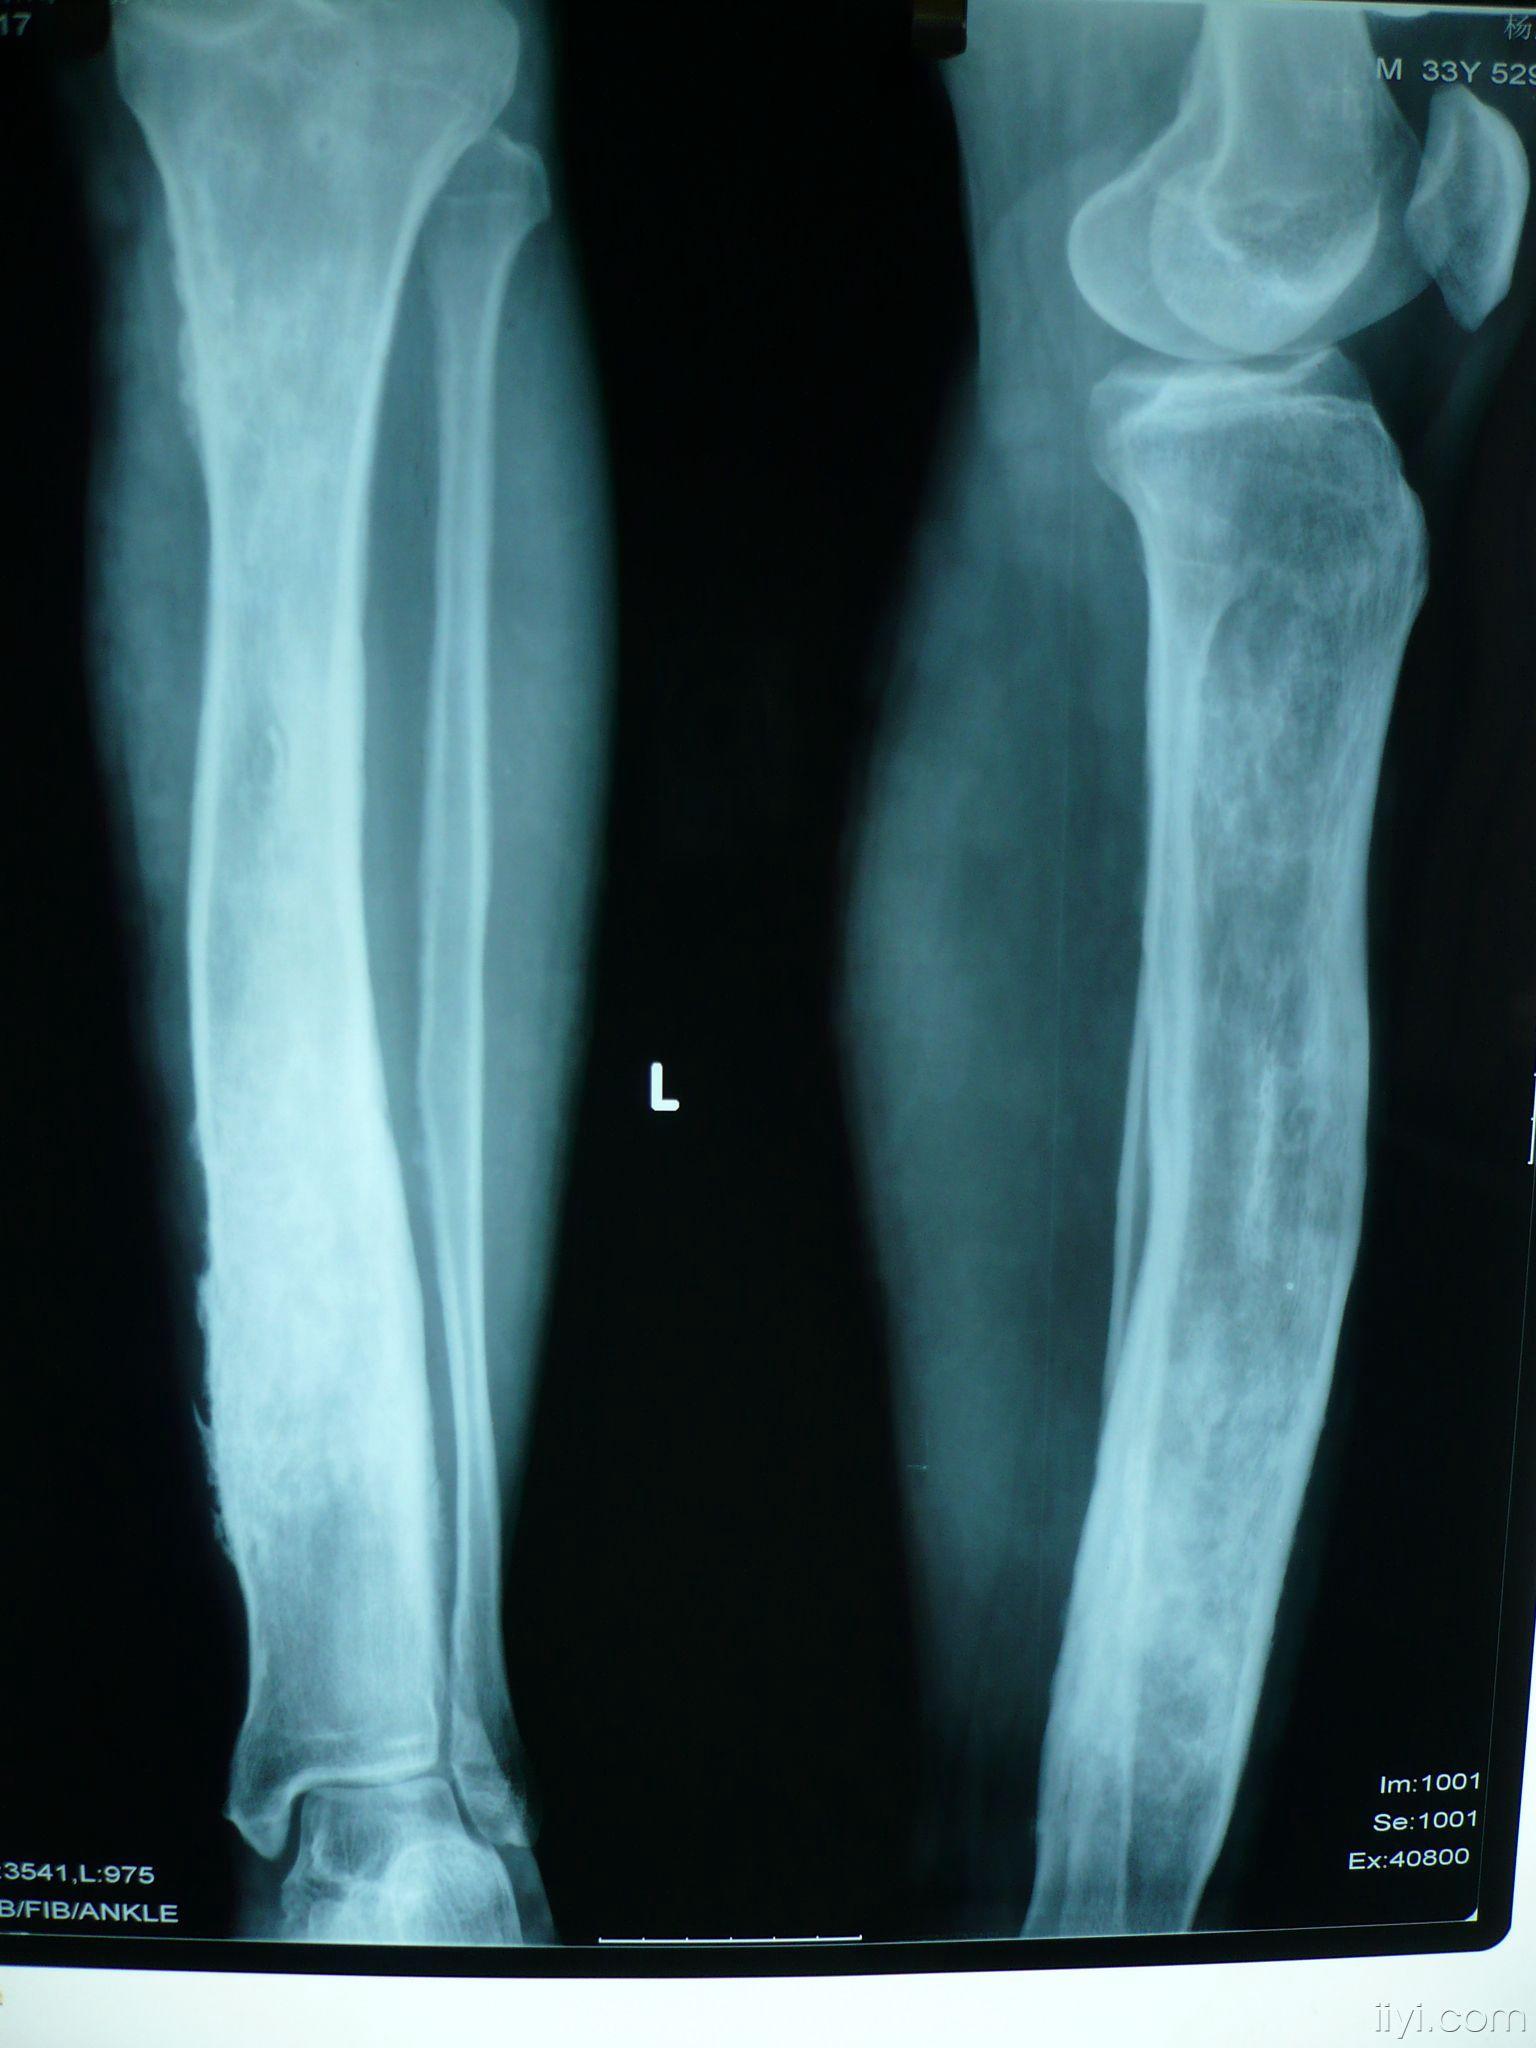

左胫骨慢性骨髓炎

这一例胫骨慢性骨髓炎大家有啥好建议